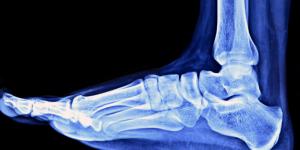

El adormecimiento o la sensación de hormigueo en los dedos de los pies es habitual en muchas personas y, a veces, se experimenta sin un motivo aparente. Suele producirse en ocasiones puntuales y sin tener mayor importancia, pero también puede ser un indicador de un problema de salud más grave.

Las razones por las que se te duermen los dedos de los pies pueden ser de origen neurológico, mecánico o vascular. Identificar la causa exacta de tu caso es fundamental para dar con la solución adecuada. Si te preguntas "¿por qué se me duermen los dedos de los pies y cómo evitarlo?", en unCOMO te recomendamos que sigas leyendo este artículo.